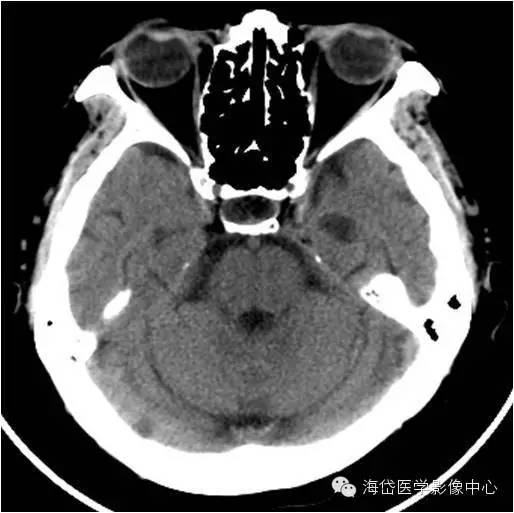

蛛网膜颗粒CT表现

CT平扫和增强均表现为静脉窦内的圆形低密度或充盈缺损,以增强后薄层扫描显示最佳。增强扫描蛛网膜颗粒的中心可有强化,为进入蛛网膜颗粒的静脉强化,或与硬脑膜窦相通的内皮细胞间隙强化所致。

平测CT值绝大多数蛛网膜颗粒和脑脊液的密度相似。少数蛛网膜颗粒可以发生钙化,钙化可以位于蛛网膜颗粒周边、中心或完全钙化。蛛网膜颗粒亦可以有颅骨迹,压迹明显者可达颅骨外板。